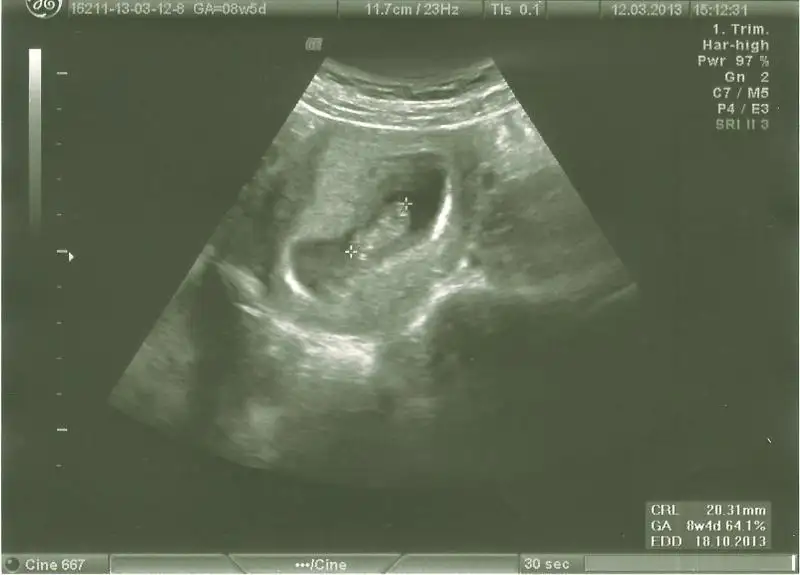

dr soylemeden siz gorun genital nub teorisi ( bebegin cinsiyeti)

bnde yorum bkliyorum kızlarr 2ncisi 11hafta bitiminde 2li tst günüydüü lütfeen

canim bu haftalarda paralel olup erkek cikan cok olduu simdilik paralel seninki 12 13 haftada bu skeil olsaydi kesin kiz derdim ama 11 haftada yorum yapamiyorum

evet bana da paralel geldi.dr da o hafta kıza benziyo dedi .ben 3.kıza hazırlıyorum psikolojimi.bir ihtimal belki rahat bir gebelik olması ve erkek belirtileri vermesi belki erkektir dedirtiyo ama nub ortada.

canım daha erken ama benimkine de bir bakın :1:

haftaya yenilerini koyacağım